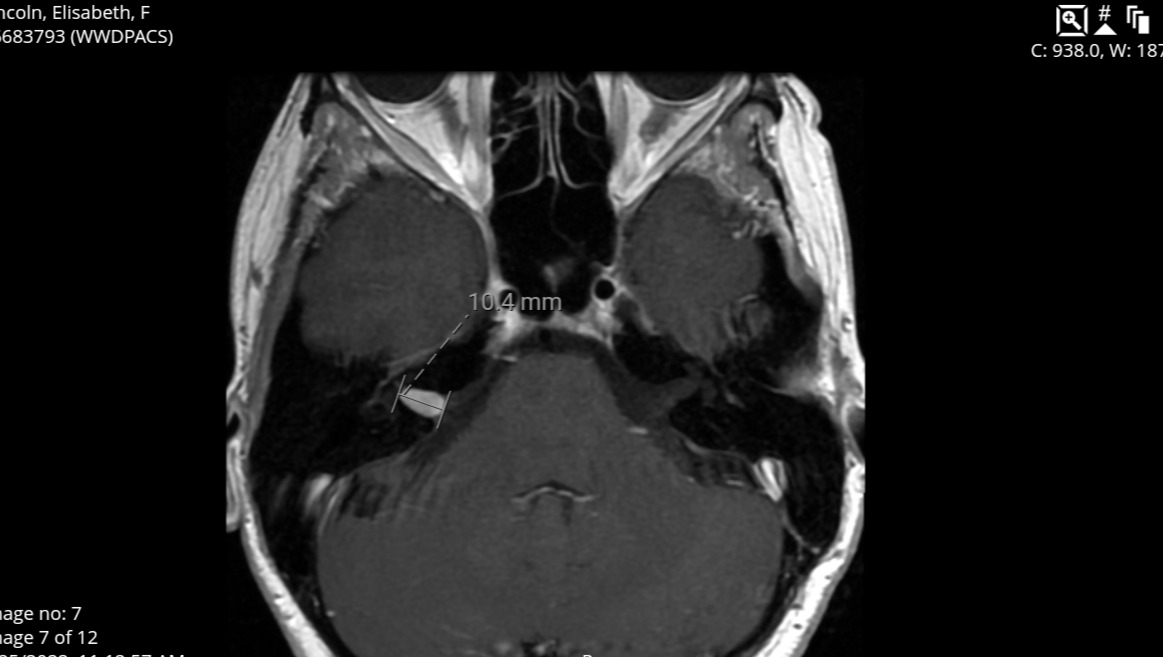

On May 25, 2022, after experiencing debilitating symptoms, I was diagnosed with an Acoustic Neuroma brain tumor.

The tumor had enveloped my auditory nerve and while small was also causing significant damage to my facial and vestibular nerves.

A retrosigmoid craniotomy to remove the tumor was performed on August 12, 2022 at Mayo Clinic in Rochester, Minnesota. This is highly invasive surgery, requiring the retraction of the cerebellum for several hours and highly skilled neurosurgeons.

I will need a yearly brain mri to monitor for tumor regrowth. My neurologist has recently prescribed physical therapy to begin late November 2023. He believes the severing of a major nerve in my neck is responsible for the majority of the chronic pain, and that massage may relieve it to a degree without the need for additional medication.